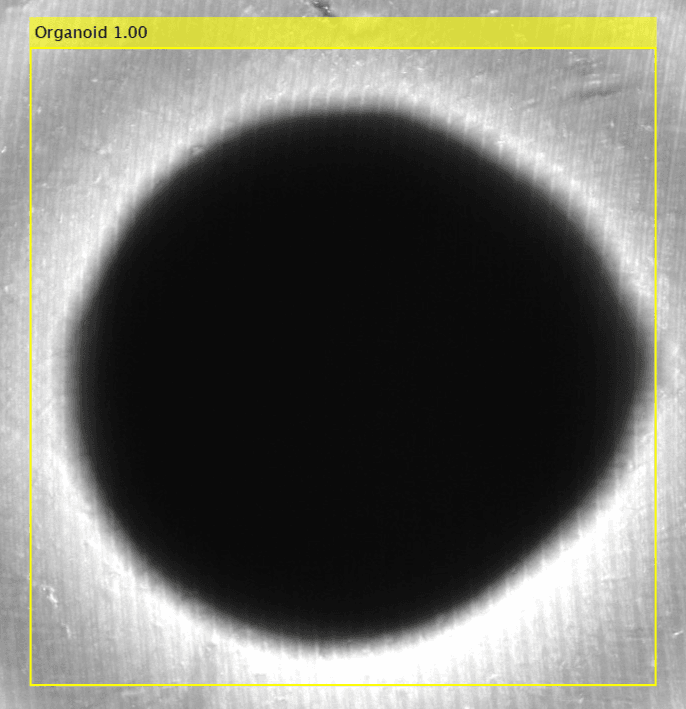

Organoids